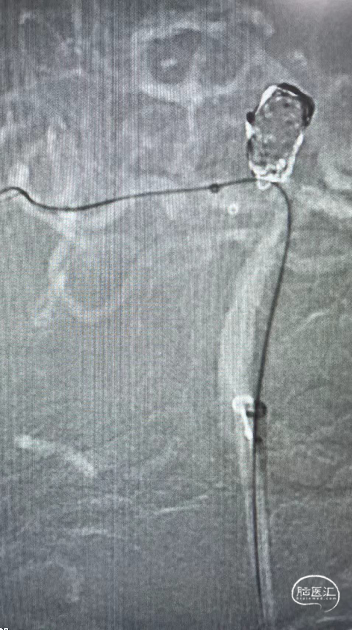

DSA:右侧P1段一6.8*9.7mm不规则囊状突起动脉瘤,远端P2段呈螺旋状蛇形动脉瘤改变。

DSA:右侧P1段一6.8*9.7mm不规则囊状突起动脉瘤,右侧A1段动脉瘤。夹层蛇形动脉瘤。

DSA:评估右侧后交通。

右侧颈内正位

术后即刻复查:远端血管通畅、支架打开良好。

术后正位复查